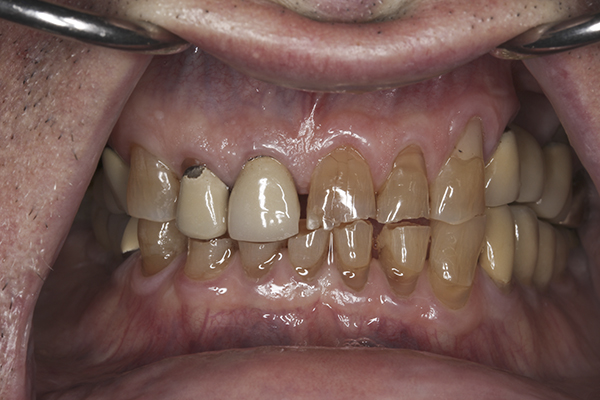

(10.) Preoperative anterior, closed view. Note the end-to-end occlusion of the anterior teeth and the wear on the incisors and centrals resulting in no anterior or canine guidance.

Figure 10

A complete examination was performed. The patient showed no signs of joint dysfunction and there was no tenderness to palpation of any of his muscles of mastication. His mandibular range of motion was within normal limits and his function was completely comfortable. Loading of the joints in centric relation was possible with no signs of tension or tenderness. The first point of tooth contact in centric relation was noted on tooth No. 3 with a 1 mm slide forward from centric relation into maximum intercuspation. Doppler auscultation of the joints showed no signs of clicking/popping or crepitus. Examination of the teeth showed significant wear, abfractions, and erosion into the dentin of the anterior teeth. The patient also had a history of fractured porcelain on his posterior restorations and crowns coming loose. An evaluation of his occlusion revealed that the patient lacked stable centric stops on all teeth. Anterior and canine guidance was non-existent, which led to no separation of the posterior teeth during protrusive and lateral movements. His maxillary and mandibular occlusal planes were also not ideal. The patient reported no airway issues while sleeping and he had a Class 1 Mallampati score. The patient was advised to consult with his physician to evaluate for an acid reflux issue.

A complete set of records was taken, including diagnostic photographs (Figure 3 through Figure 16), diagnostic impressions, a centric relation bite record, and a facebow transfer. The models were mounted onto an articulator and, along with the photographs, a preliminary workup of the case was completed. An ideal treatment plan consisting of a fullmouth rehabilitation with full-coverage restorations to idealize the planes of occlusion and to properly restore the anterior teeth was presented to the patient. The patient was not interested in extensive work on his posterior teeth because of his age and the fact that he was only interested in “something that will last another 10 years because that’s about how long I’ll be around.” He was only concerned with addressing the anterior teeth and would not accept a treatment plan replacing the restorations on his posterior teeth. Because the author wanted to help the patient with his esthetic concern while still addressing the functional issues, an alternative compromise treatment plan was agreed upon, which involved definitive full coverage restorations in the anterior and composite bonding in the posterior. The patient was fully aware that this treatment plan was a compromise and that the posterior composites will most likely require repair over time. By stabilizing the anterior contacts, anterior guidance, and canine guidance, the author felt comfortable placing bonded composite restorations on the posterior teeth to improve the plane of occlusion. The author also suggested the use of a nighttime occlusal appliance, but the patient refused this option. A guard worn at night would have increased the longevity of the posterior composites, as well as further protected the anterior restorations.